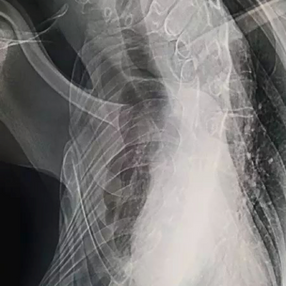

The chest wall was severely deformed, with the left side protruding both forward and backward, and the development of the right side halted with pronounced scoliosis. Meanwhile, the heart and lungs were severely compressed.

The patient, a 22-year-old male, suffered from pneumonia when he was 5 year-old, which later developed into a right chest wall abscess. After six months of treatment, the abscess cleared up, and the patient has not experienced any significant symptoms since then. However, his right chest wall gradually sank, and almost stopped developing. Meanwhile, his left chest wall gradually enlarged and became noticeably deformed, leading to severe scoliosis. In the past two years, the patient has frequently experienced breathing difficulty, chest tightness, and palpitations, which become more pronounced after physical activity.